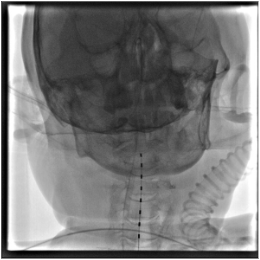

图片

在详细向家属做了解释说明并取得同意后,神经外科专家为患者短时程脊髓电刺激治疗。

脊髓电刺激术(SCS)是将脊髓刺激电极安放于椎管的硬膜外腔,通过电流刺激脊髓后柱的传导束和后角感觉神经元,从而达到治疗疼痛或其它疾病目的的一种治疗方法。

近年研究发现,高位脊髓电刺激,对于慢性意识障碍患者有促醒作用。

其原理是,通过高位颈髓发送电刺激脉冲,增加脑干起始的上行网状激活系统的神经冲动,改善神经传导状态,使得神经细胞电活动增强,调节交感神经的活动,增强全脑血流,改善糖的代谢水平,并且增加神经递质多巴胺、肾上腺素的释放,促进患者意识水平的提高。